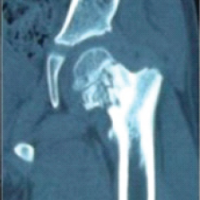

A 50-year-old right-hand dominant male presented to the orthopedic office for evaluation of chronic right elbow pain. He states this has been ongoing since he sustained an injury, while in the military, about 7 years ago. Over this period, he underwent 7 different surgeries related to this injury, with the most recent procedure in January of 2011. He noted considerable pain, stiffness, and significant difficulty performing tasks at work and activities of daily living. His pre-operative Visual Analog Scale (VAS) pain score was a 10 out of 10, mayo elbow performance score (MEPS) was 15/100 (<60 indicating poor performance), American shoulder and elbow surgeons (ASES) score of 18/100, and disabilities of the arm, shoulder and hand (DASH) score of 70/100 with additional noted severe difficulty performing his required work activities as a sports photographer. He also indicated that he was unable to participate in bowling, his sport of most importance, on pre-operative questionnaires. Radiographs and a computed tomography scan were obtained, which demonstrated advanced degenerative changes in the radiocapitellar and ulnohumeral joints (Fig. 1). Given his age, job requirements, and lifestyle, we felt the patient would not be a great candidate for a total elbow replacement given the activity and post-operative weight restrictions. Instead, we recommended treatment with an interpositional arthroplasty for the treatment of his post-traumatic osteoarthritis (Figs. 2 and 3).